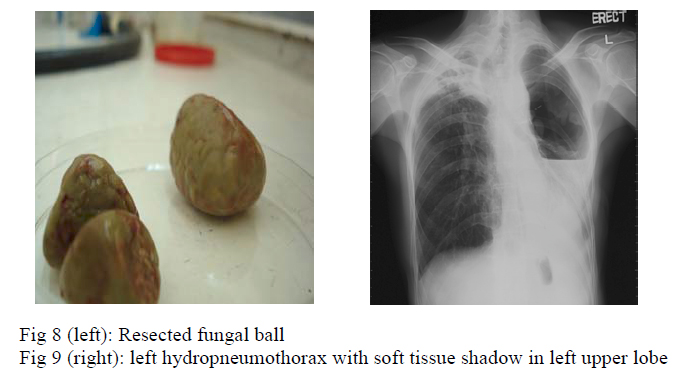

Left upper lobe lobectomy was performed in June, 2006 but it was complicated by aortic perforation, which was repaired successfully. Histology of the resected tissue (fig 8) showed caseous granulomatous inflammation, destroyed bronchial wall with inflammatory cell infiltration, and fungal mycelium was seen. Culture of tissue grew scedosporium apiospermum. Haemoptysis subsided after the surgery and voriconazole was given for 8 weeks.

Eight months later, patient was readmitted because of dyspnoea, purulent sputum and fever for three days. Chest radiograph showed left hydropneumothorax with soft tissue shadow at the left apical region (fig 9). Patient remained in respiratory failure despite chest drain insertion and required invasive mechanical ventilation. He developed septic shock and succumbed 2 days after admission. Pleural fluid microscopy showed large number of white blood cells and gram negative bacilli, with few gram positive cocci. Culture showed moderate growth of Scedosporium apiospermum.